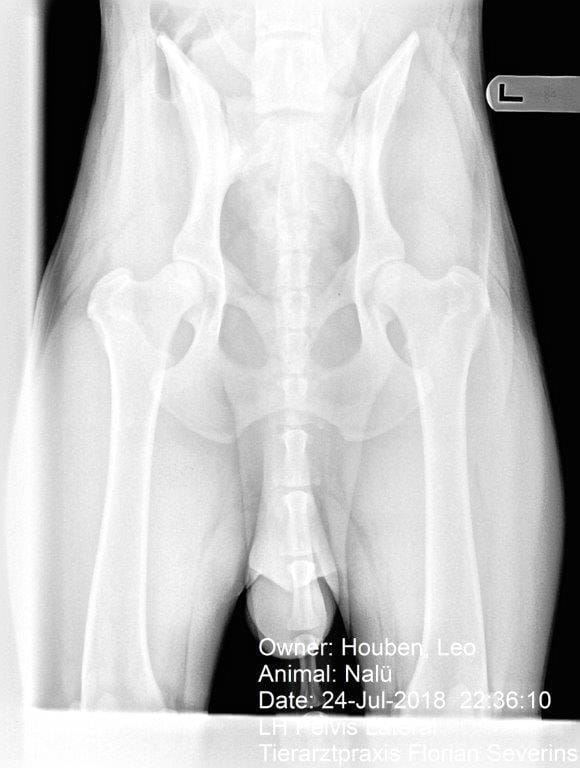

NALU-SOLD

Nalu is a 25 month old German Shepherd import. Nalu has excellent hips. He is a semi-social dog with excellent drive and environmentally sound. His grip is firm, full and calm. He is available finished for dual purpose narcotics